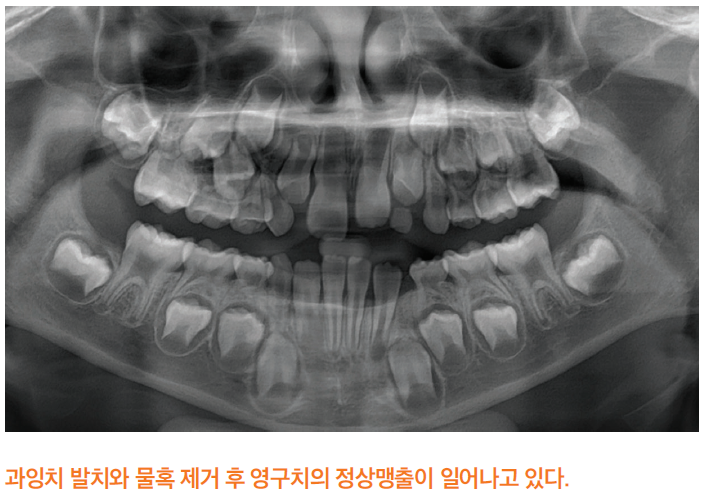

과잉치의 치료는 외과적 수술을 통해 제거하는 것입니다. 발치 시기는 과잉치가 영구치의 맹출을 명확히 방해하거나 낭종 형성 등의 병리적 문제가 있을 때 조기 발치를 적극적으로 고려합니다. 그 외에는 정기적인 방사선 촬영을 통해 과잉치의 상태와 주변 영구치의 발육 정도를 평가하여 주변 영구치의 뿌리가 충분히 성장한 이후 수술을 결정합니다.

수술적 접근법은 과잉치의 위치와 맹출 방향에 따라 다르며, 과잉치가 매우 깊이 매복되어 있는 경우에는 전신마취 하에 발치를 시행하기도 합니다. 또한 발치 후에는 정기적인 추적관찰을 통해 영구치의 맹출 상태를 지속적으로 평가해야 합니다. 아이의 협조도가 좋은 경우 국소마취 하에 발치를 시행할 수 있으나, 연령이 어리거나 치과치료에 대한 불안감이 높은 아이, 또는 수술의 난이도가 높은 경우에는 진정법이나 전신마취를 활용하여 아이에게 심리적 안정감을 제공하면서 안전하고 효과적으로 수술을 진행할 수 있습니다.